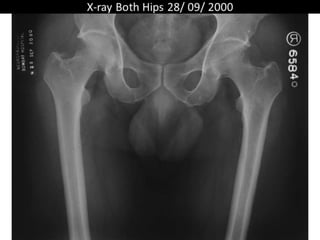

The document presents a detailed case study of a patient with transient osteoporosis of the hip (TOH) and spontaneous osteonecrosis of the knee (SONK) treated at Choithram Hospital & Research Centre in India. Over 20 years, the patient experienced multiple episodes of TOH and SONK with no history of trauma or co-morbidities, resulting in resolutions and recurrences of conditions. The information is intended for orthopedic surgery students and highlights personal experiences and case collections, with a disclaimer regarding content usage and potential controversies.